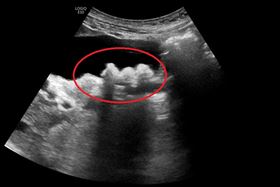

老婆腹痛!他拿超音波照問:腸胃炎?

難道這是「假求問,真放閃」?一名男網友著急的分享出1...